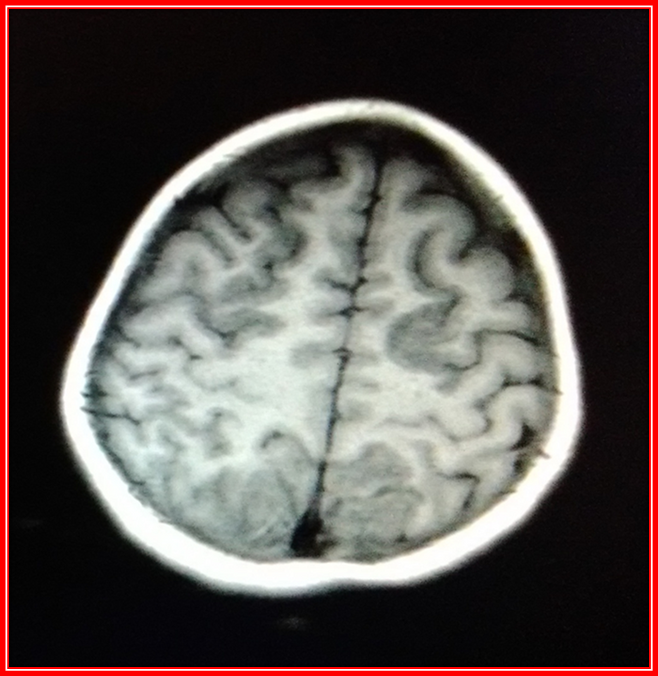

The following are images of Simple Brain Magnetic Resonance, of the patient of the case already discussed.

Brain Magnetic Resonance Simple cut T1.@anaestrada12

CT scans show changes in the signal intensity of hypointense behavior in T1 and Hyperintense in T2 with perilesional edema, including cortical region, sub-cortical frontal lobe, parietal and bilateral occipital.